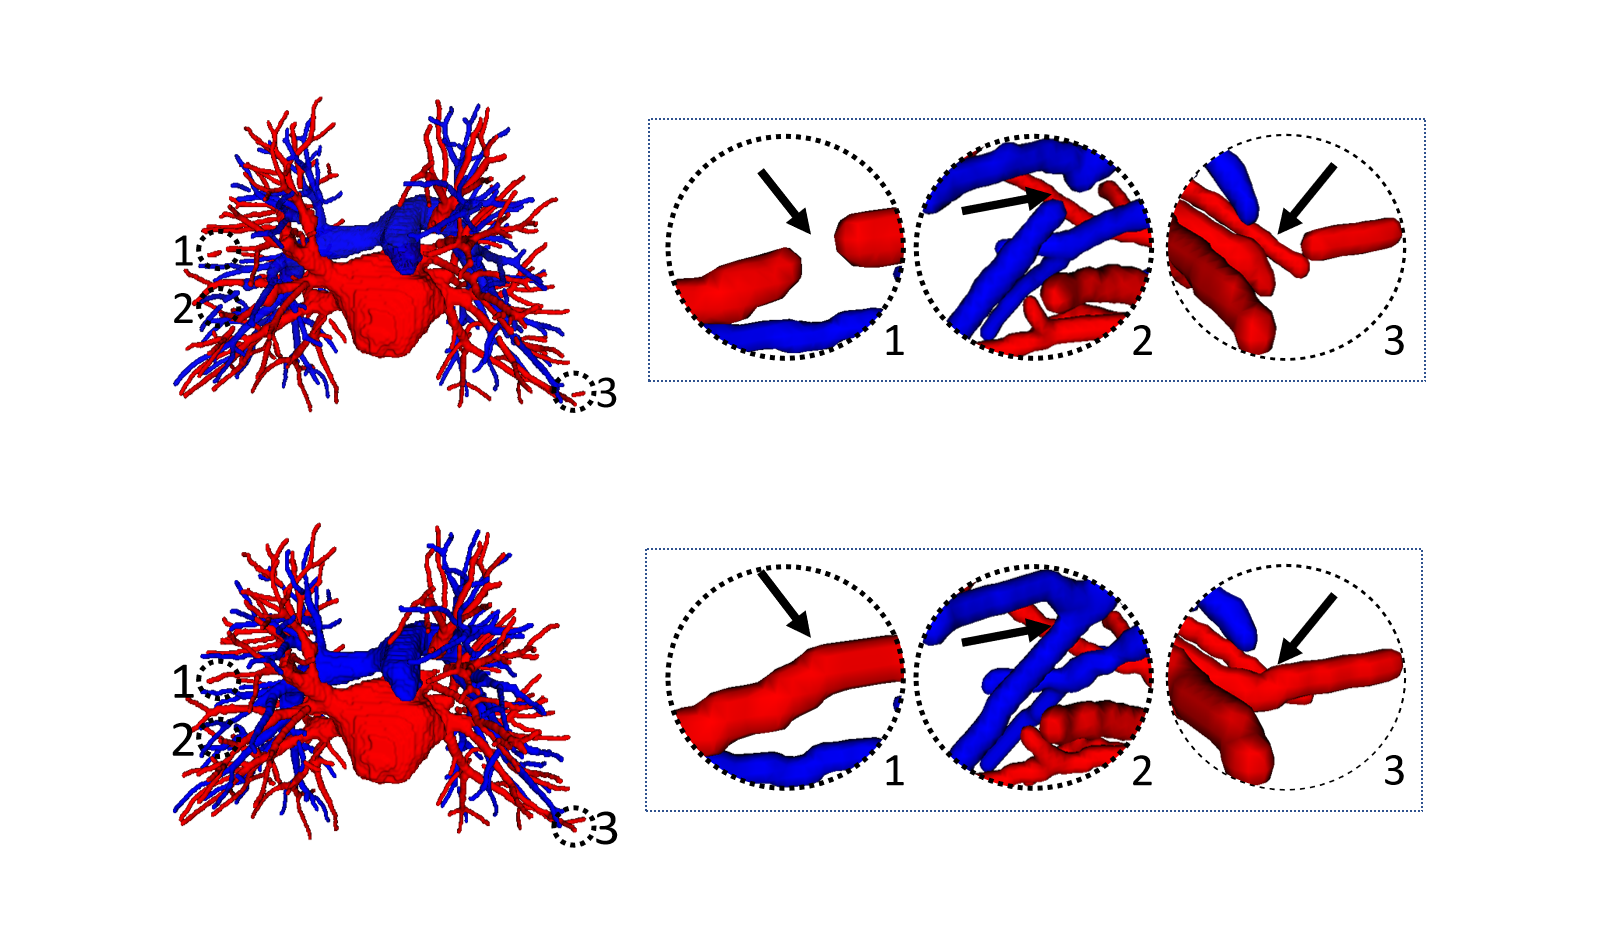

To prove that the proposed topology optimizer is reasonable, we design different topology strategy optimizer to compare and analyze the experimental results. This approach includes the following: the precision of Twin-Pipe network (based on particle), the precision of topology branch refining (based on branch), the precision of topology subtree refining (based on subtree), and the refinement precision of the proposed topology optimizer. Table 3 shows an overview of the accuracy in all cases of the different topology strategy optimizers and reports on the sensitivity and specificity. The table 3 shows that our method is superior to branch-based and subtree-based topology optimizers, whose accuracies are 96.2%, 95.3%, and 93.2%, respectively.

Finally, the topology optimizer extracts the topology subtree and topology branch refinement results by the method in Section 2.3. The results of a topology subtree and topology branch are shown in Fig. 9. Then, we use topology subtrees and topology branches for postprocessing. As shown in Table 3, the proposed topology optimizer is superior to the subtree-based and branch-based topology optimization in accuracy. Fig. 14 and 15 show the reconstructed results of different topology strategy optimizers. The results in Fig. 14 show that when the number of points on the branch is small, and the branch-based topology optimization method is prone to predict errors. This finding is mainly because the branch-based refinement strategy focuses on the relationships within the branches and ignores the topological relationships between branches. As shown in Fig. 15, topology optimization based on subtree strategy is prone to prediction errors in the case of arterial-vein intersection. This finding is mainly because the arterial/venous intersection point in the extraction process of topological subtree is easily mistaken for the bifurcation point of arterial subtrees due to the complex structure of the vascular tree, arteries and veins interweave, and finally the venous branches are classified as arterial subtrees, resulting in the classification error.